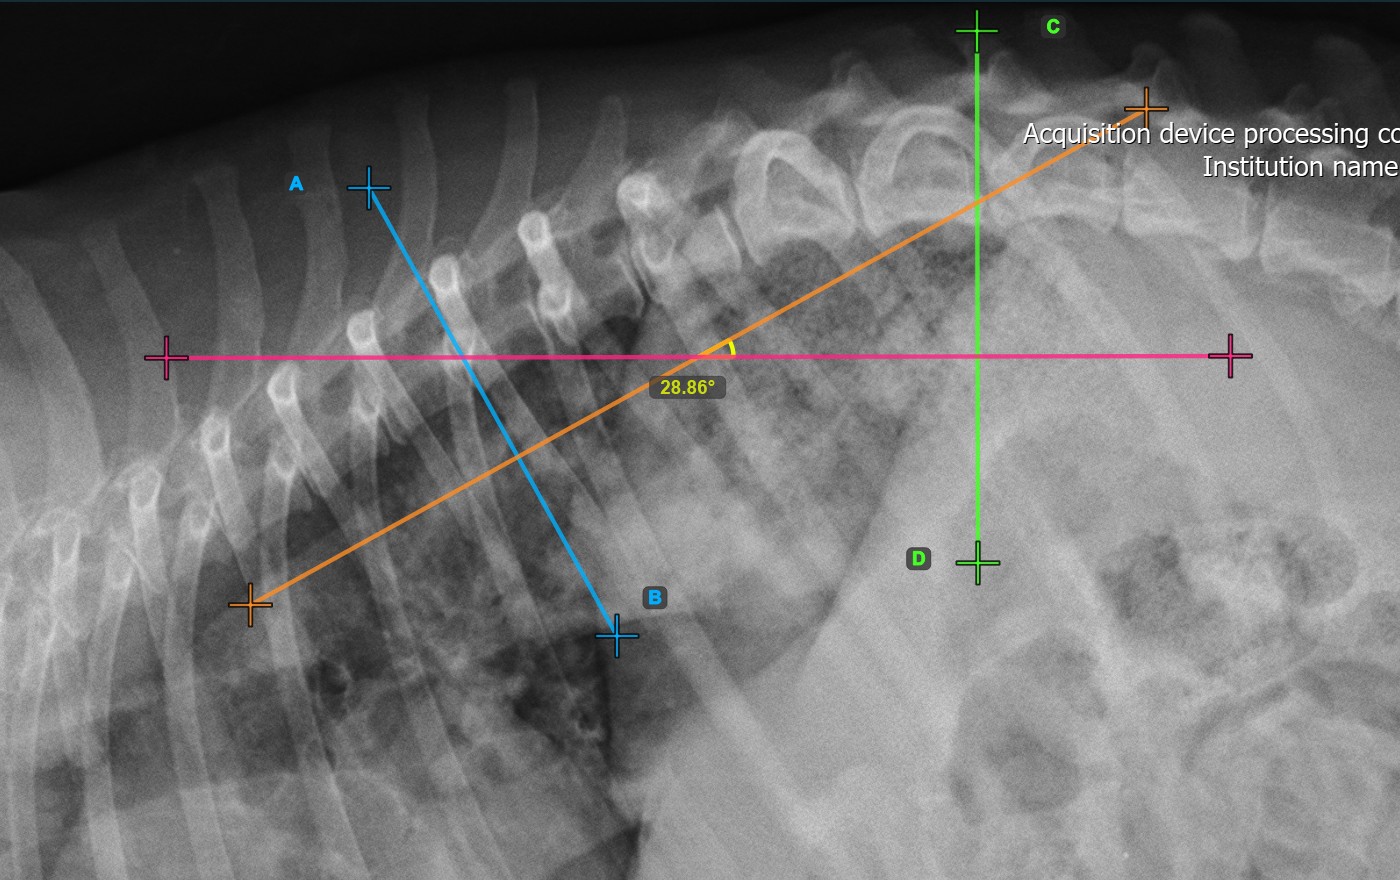

The Cobb Angle measurement will be automatically calculated and completed once the two vertebral lines are placed, indicating the angle of spinal curviture in degrees.

The image below represents a typical placement of the second vertebral line.